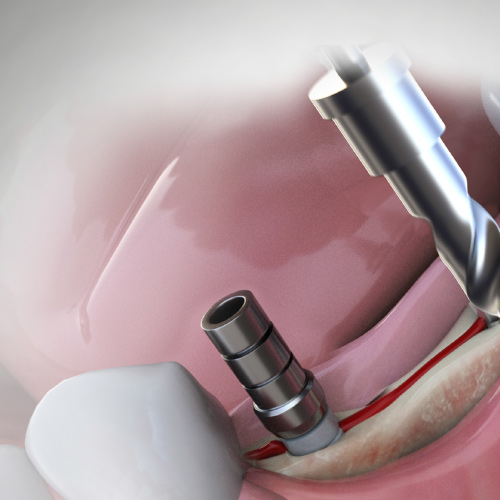

Implantology Pathways

This Compendium eBook features features a continuing education (CE) article on the use of subcrestal implantoplasty for the treatment of peri-implantitis. This eBook also includes a case report article on a novel, minimally invasive technique to reconstruct class III sockets with simultaneo...

Implantology Updates

This Compendium eBook features a continuing education (CE) article on hard- and soft-tissue augmentation for implant therapy in the esthetic zone. This eBook also includes a case report article on a minimally invasive technique for the reconstruction of class III sockets with simultaneous i...

Implantology Advances

This Compendium eBook offers a continuing education (CE) article on partial extraction therapy in implant dentistry, with an emphasis on the biologic and anatomic conditions necessary for optimal outcomes with implant surgery. This eBook also includes a case report describing a strategy for...